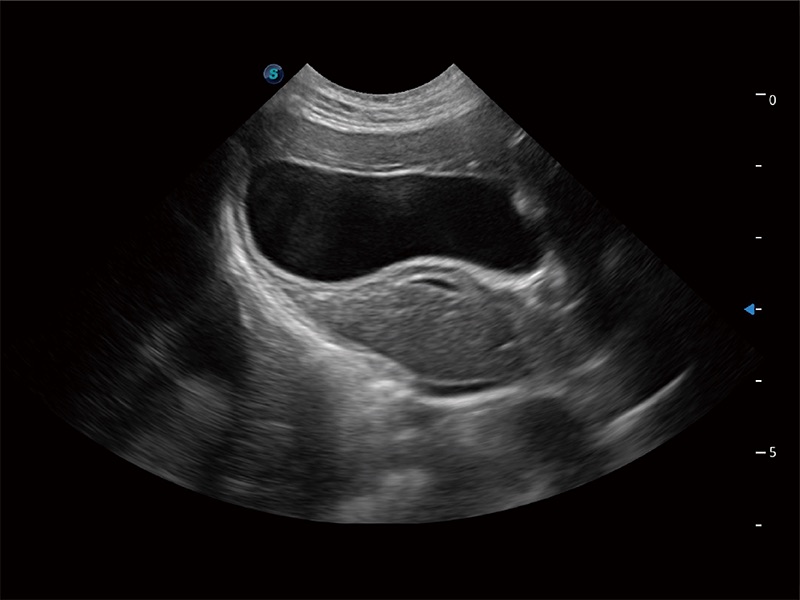

(猫)胆囊

• Auto Bladder 膀胱自动测量